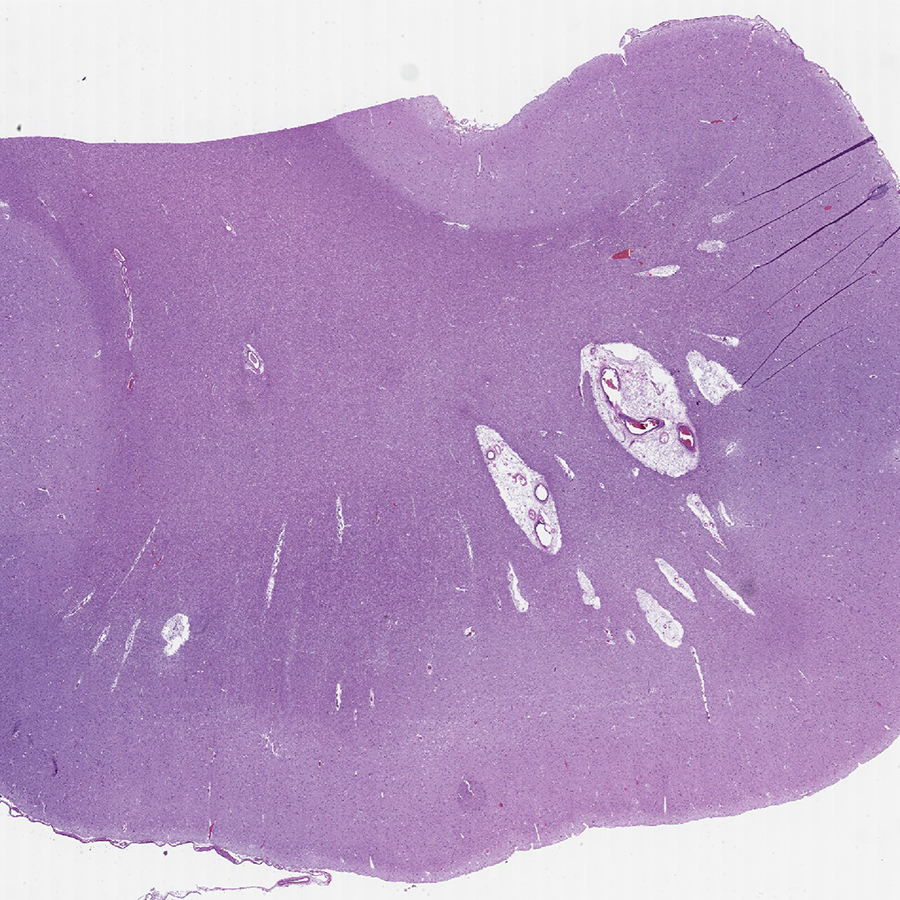

This is subcortical arteriosclerotic encephalopathy, a.k.a. Binswanger's Disease. Resembles

#Alzheimers clinically, but it's caused by bad#arteries.#Exercise and healthy diet are your best protection!#pathology#neuropath#pathtwitterpic.twitter.com/bgE5j6hV8y